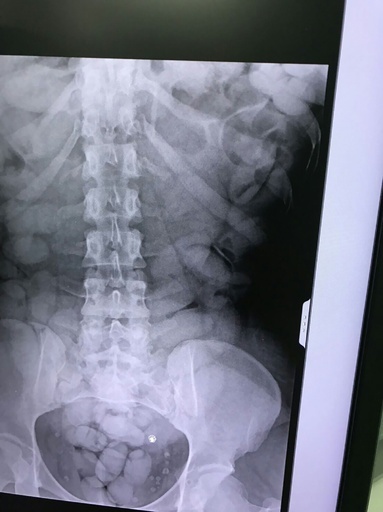

【12月4日 AFP】英国で1日朝、第2次世界大戦(World War II)時の対戦車砲弾が直腸に入った男性がグロスターシャー王立病院(Gloucestershire Royal Hospital)に救急搬送され、警察と軍の爆発物処理班が出動する騒動となった。

砲弾は後に第2次大戦時の対戦車砲弾だと確認された。国防筋がサン紙に語ったところによると、砲弾は57ミリ対戦車砲用で、長さ17センチとされる。